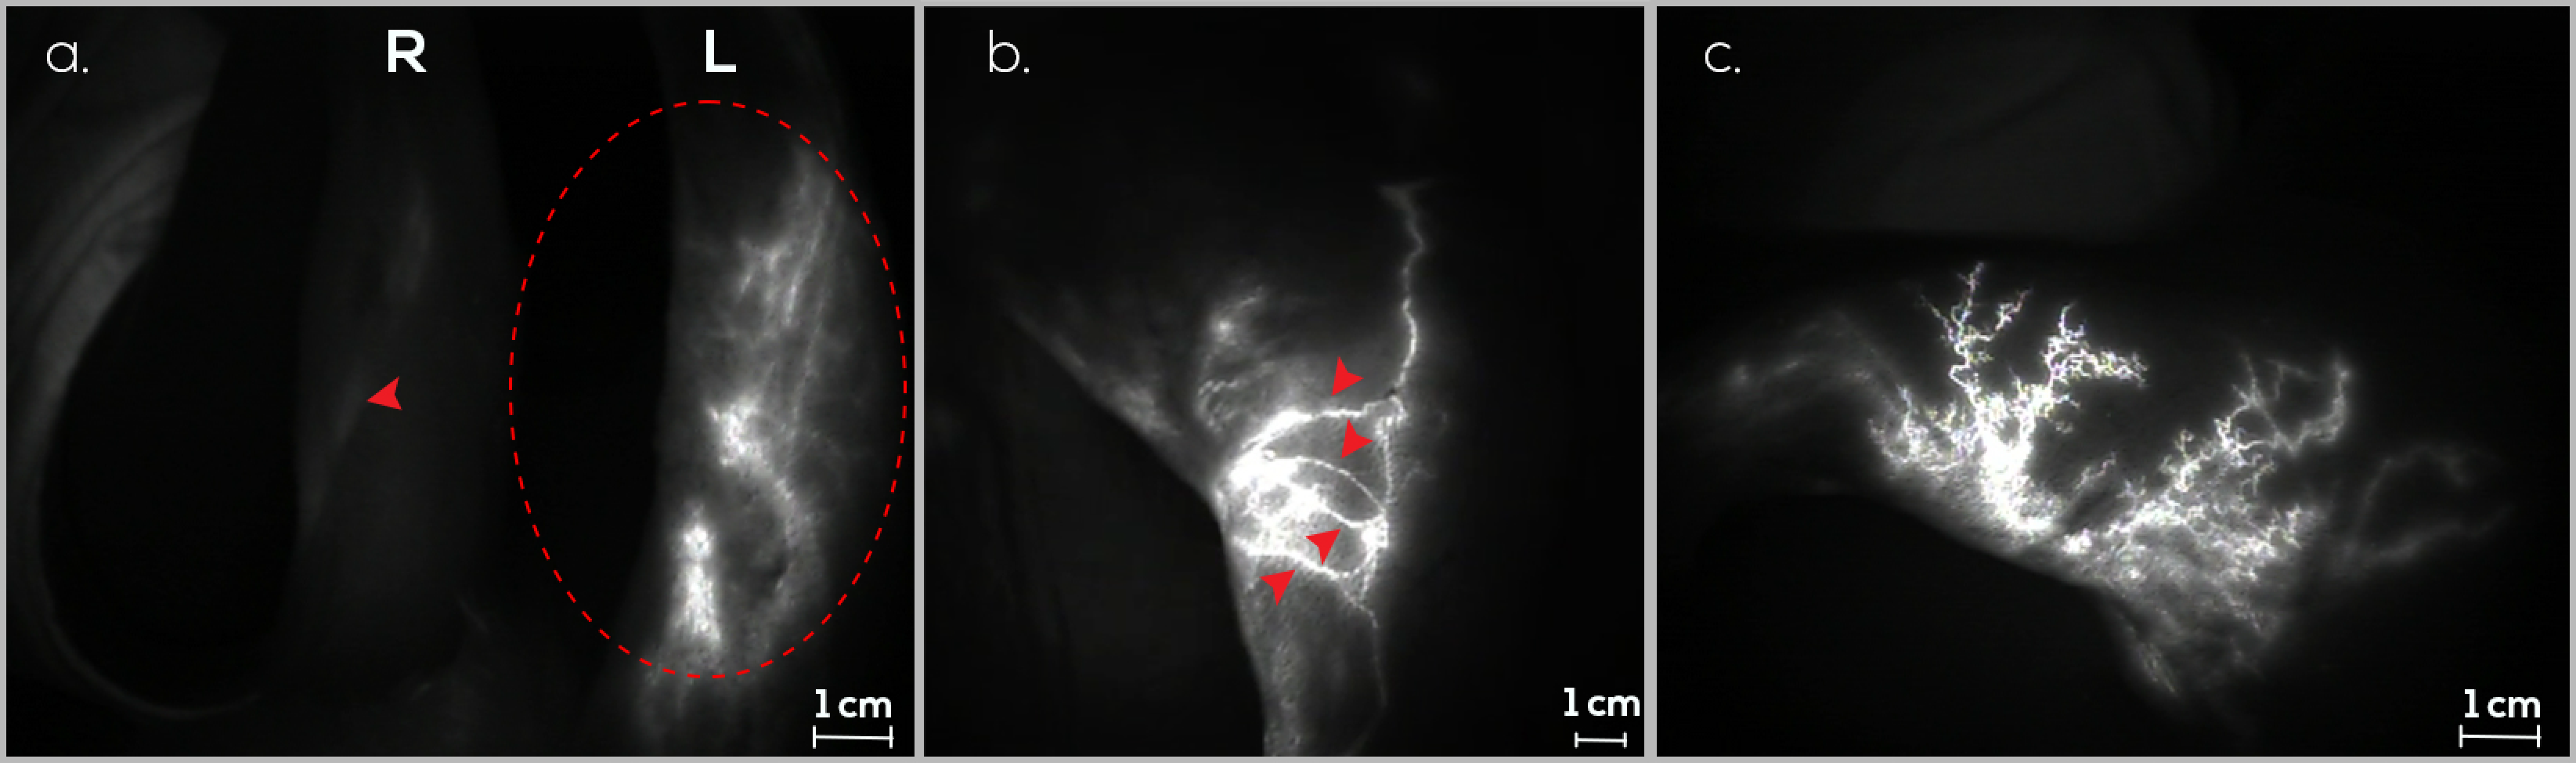

3.2. Preventive Group (G2)

3.3. Control Group (G3)

3.4. Follow-Up Assessments